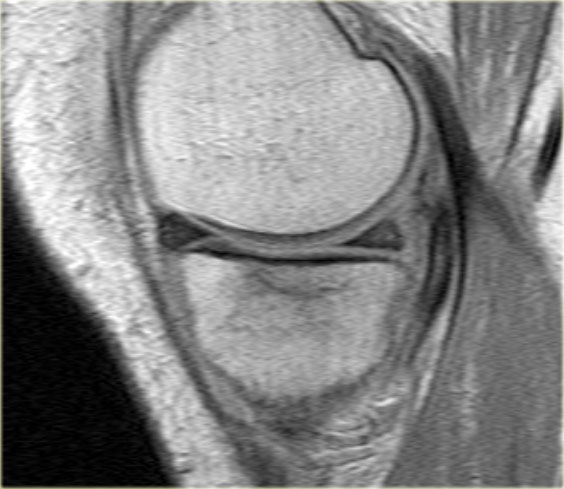

- Một số bất thường ở phần sau.

- Phần sau di chuyển về phía đuôi (caudal).

- Trong hố gian lồi cầu là điểm nối giữa mảnh di lệch và phần còn lại của sừng sau.

Bên trái là một trường hợp sụn chêm lật khác.

Lần này ở phía trong (medial).

Một phần sừng trước bị lật ra phía sau.

Chỉ một phần nhỏ của sừng trước được nhìn thấy ở phía trước.

Hầu hết các trường hợp sụn chêm lật xảy ra ở phía ngoài (lateral).

Dây chằng chéo trước (ACL) ngăn mảnh sụn chêm di chuyển hoàn toàn vào hố gian lồi cầu.